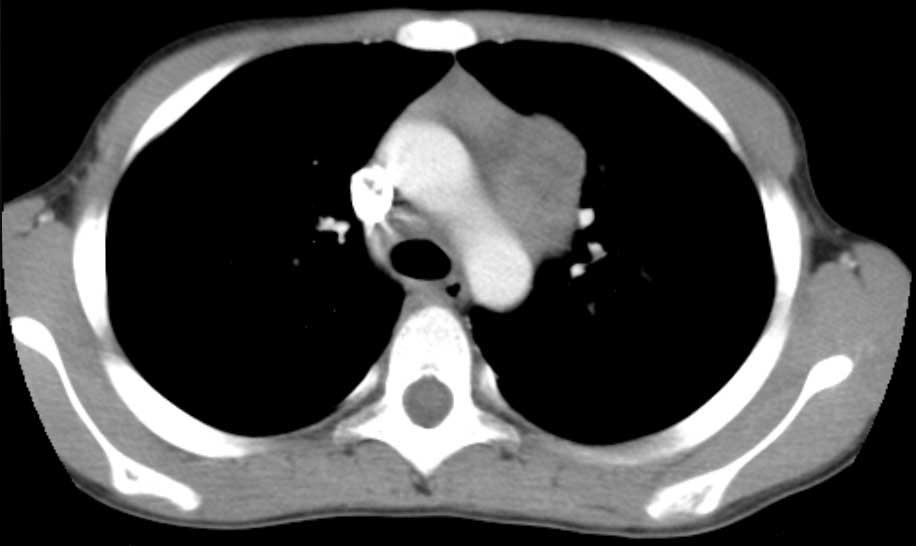

Hình ảnh này của một nam bệnh nhân 60 tuổi có khối trên X-quang ngực.

Sinh thiết dưới hướng dẫn CT được thực hiện do nghi ngờ ung thư phổi.

Hình ảnh

Có một khối tạo hang ở thùy dưới phải.

Lưu ý cũng có các đậm độ dạng “cây nảy chồi” xung quanh khối.

Lao được xác nhận bằng sinh thiết.